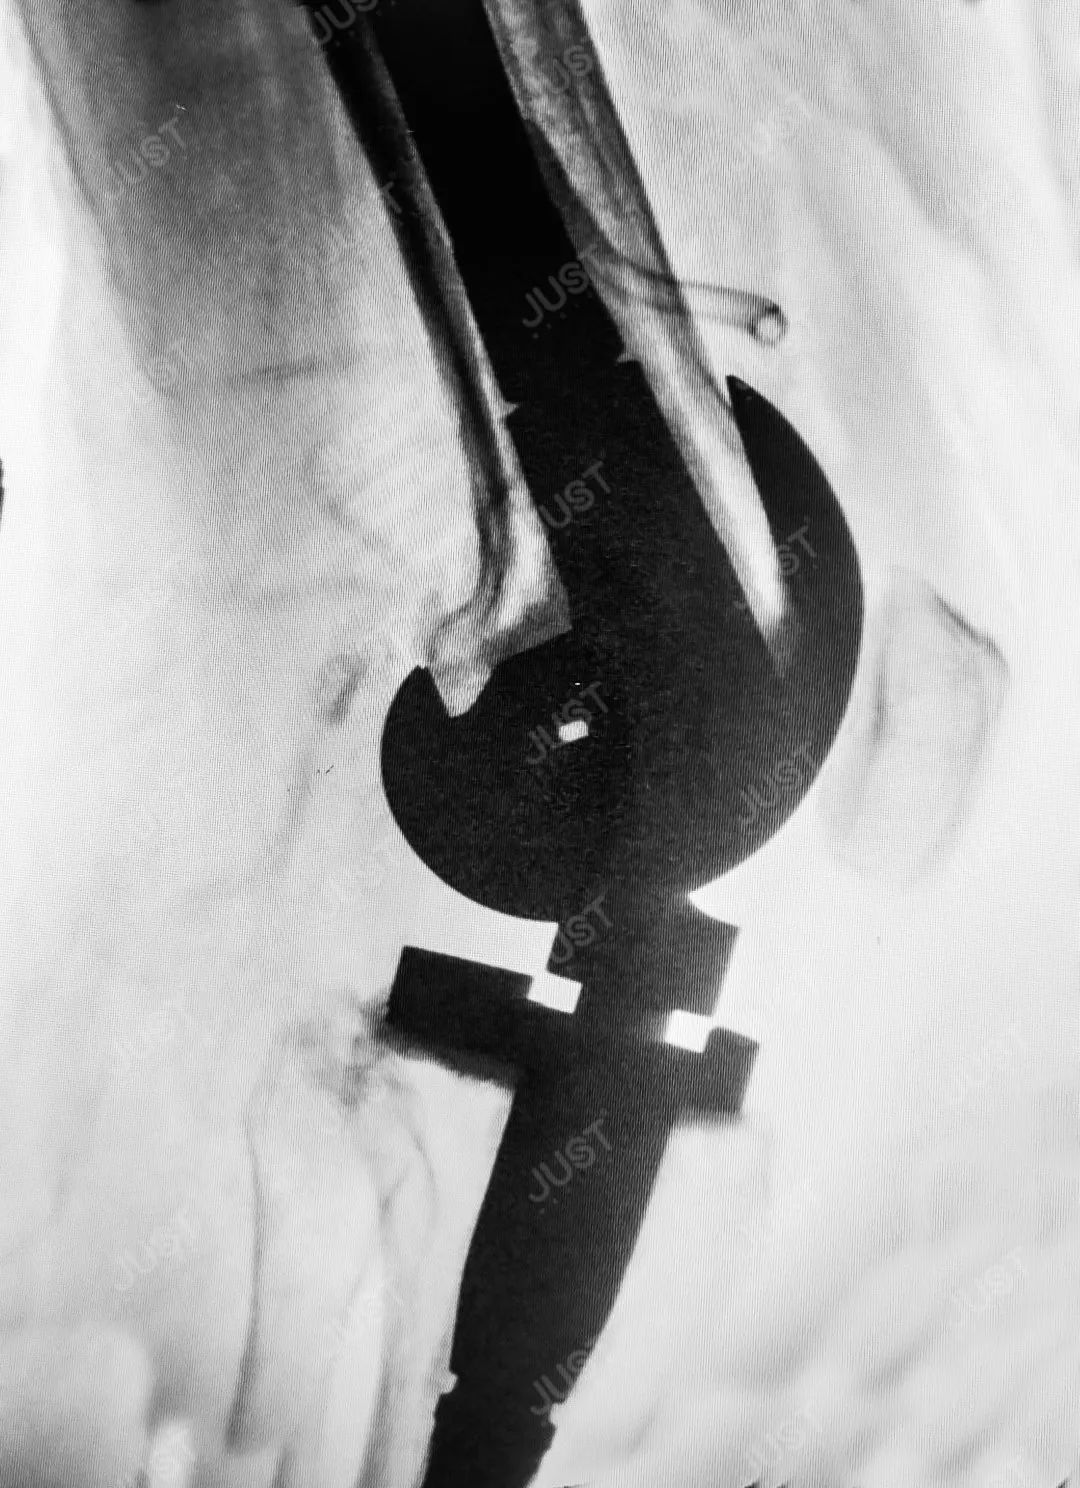

术中透视片